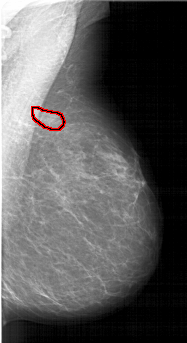

A_1610_1.RIGHT_MLO

RIGHT_MLO LINES 6166 PIXELS_PER_LINE 3361 BITS_PER_PIXEL 12 RESOLUTION 43.5 OVERLAY

FILE: A_1610_1.RIGHT_MLO.OVERLAY

TOTAL_ABNORMALITIES 1

ABNORMALITY 1

LESION_TYPE MASS SHAPE ASYMMETRIC_BREAST_TISSUE MARGINS ILL_DEFINED

ASSESSMENT 4

SUBTLETY 3

PATHOLOGY BENIGN

TOTAL_OUTLINES 1

BOUNDARY